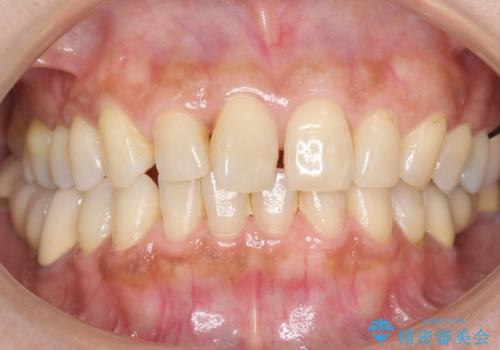

歯が痛い 深いう蝕により神経が死んでいる 50代女性

- 奥歯の痛みを主訴に来院された患者様です。

精査したところ、ブリッジの支台歯となっている左下の奥歯(左下7)は大きなう蝕により神経が死んでいました。

根管治療後、メタルボンドブリッジによる補綴治療を行いました。

自然な仕上がりと咬み心地に喜んで頂けました。

クラウンの種類:メタルボンドクラウン エコノミー